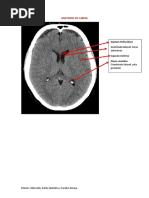

AB

A. Cerebelosas Superiores

Par craneano III

CC: cisternas crurales

CIP: cisterna interpeduncular

CA: cisterna ambiens

CC

CIP

CA

Par III

CCU

CVS

Contiene:

Art. Cerebral posterior (P4)

Gran Vena de Galeno

IV par craneal(origen)

CCU: cisterna cuadrigeminal

CVS: cisterna vermiana superior

CR: cisterna retropulvinar

CCC: cisterna del cuerpo calloso

3V: tercer ventrculo

CR

CCC

CR 4V

3V